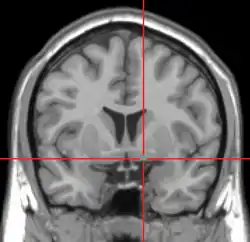

MRI showing a coronal plane of the head with marks showing the location of the substantia innominata, the region in which the nucleus basalis is found.